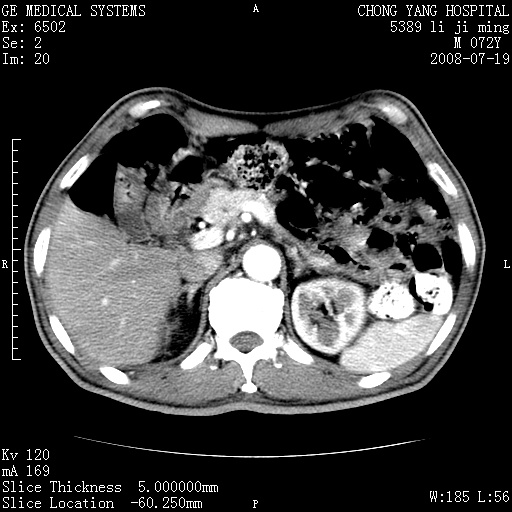

以下是引用zjzjr在2008-7-19 20:57:00的发言:[br]胰头增大,边缘模糊,周围可见渗出影,右侧肾前筋膜增厚.支持胰腺炎.

以下是引用yangyudong333在2008-7-20 6:56:00的发言:[br]胰腺增大尤以胰头明显,边缘模糊,周围可见渗出影,右侧肾前筋膜增厚,肠管於涨.支持胰腺炎

以下是引用不学无术在2008-7-19 23:15:00的发言:[br]胰腺增大尤以胰头明显,边缘模糊,周围可见渗出影,右侧肾前筋膜增厚,肠管於涨.支持胰腺炎